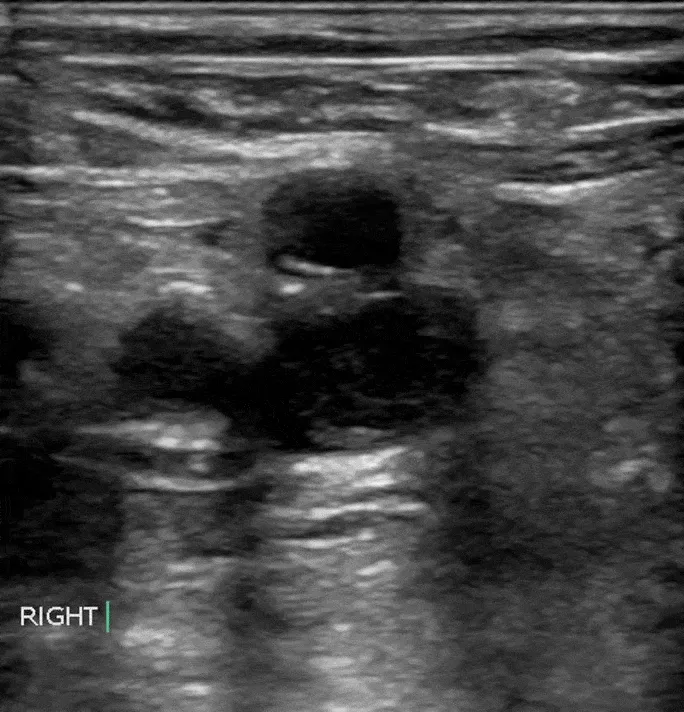

- Compression Ultrasonography (CUS): Gold standard. Non-compressible vein = DVT.